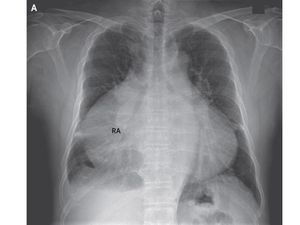

Sebelum Terlambat, Yuk Cegah Sakit Jantung dan Pembuluh Darah dengan Cara Ini

Sakit jantung dan pembuluh darah tidak hanya dialami orang tua, namun juga yag berusia muda. Sebelum terlambat, yuk dicegah!